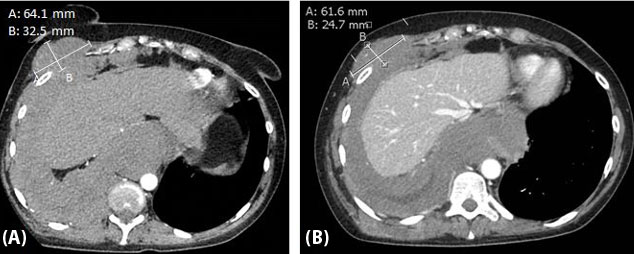

Figure 2: Right chest wall mass stability from February 2021 to August 2021. (A) Mass measuring up to 64.1 × 32.5 mm in February 2021. (B) Mass measuring up to 61.6 × 24.7 mm August 2021.

She was referred to and evaluated for clinical trials at a cancer center of excellence, for which a phase 1 oral checkpoint inhibitor was offered even though her PD-L1 tumor proportion score of 0%. She ultimately opted to continue therapy locally and was started on similar treatment with nivolumab and cabozantinib. While on combined therapy, she received surveillance imaging at three-month intervals. She tolerated combined nivolumab and cabozantinib therapy well with only grade 1 toxicity of diarrheal symptoms that was manageable with supportive therapy. Remarkably, first interval imaging demonstrated a decrease in the size of a right mediastinal lymph, dominant right chest wall nodule, and dominant right lung nodule decreased from 6.4 × 3.3 cm to 6.2 × 2.5 cm, representing an approximate 25% size reduction. She achieved a maximal response of approximately 30% decrease in tumor burden and stable disease achieved for almost eight months until the disease again progressed (Figure 2). She then opted to discontinue treatment and pursue hospice and passed shortly after.